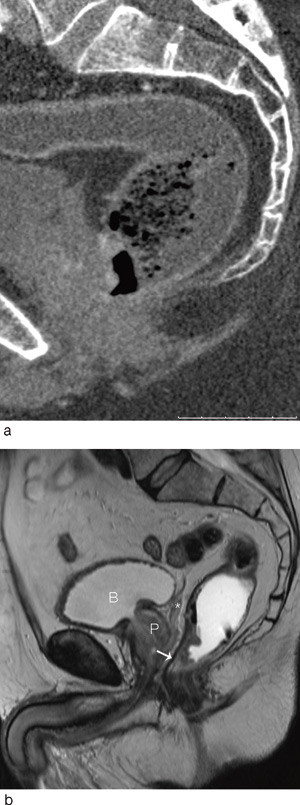

Multidetektor-CT

Bruk av CT i utredningen av fjernmetastaser ved kolorektal kreft er en godt etablert metode. CT-undersøkelsens rolle i den lokoregionale utredningen av rectumcancer er betydelig mer usikker. Studier fra de senere år har vist relativt dårlige resultater når det gjelder evaluering av perirektal tumorspredning, med en nøyaktighet på 52 – 74 % (6, 7, 12). Med MDCT-maskiner med minst 16 kanaler har man fått muligheten til å ta tynne bildesnitt som kan rekonstrueres i alle plan med samme gode bildekvalitet (fig 1, fig 2). Slik kan man få bilder parallelt og perpendikulært til tumors lengdeakse, analogt til MR-undersøkelsen. Det er vist at bruken av slike rekonstruerte bilder signifikant bedrer evalueringen med multidetektor-CT (13). Det finnes få studier der man har sammenliknet MDCT-undersøkelse med andre metoder ved rectumcancer, men resultatene så langt synes å være lovende (14) – (17).

Man venter snart resultater fra en ny, stor multisenterstudie i Nederland der bruk av CT-undersøkelse ved rectumcancer evalueres. I en nyere artikkel av Beets-Tan og medarbeidere refereres det til preliminære resultater som viser at MDCT er likeverdig med MR i øvre/midtre del av rectum, mens MR er overlegen i nedre del (18). I forhold til MR har CT dårligere evne til å skille bløtdelssjiktene fra hverandre i dette området, hvor subtile detaljer som 1 – 2 mm infiltrasjon kan skille en T2-tumor fra en T4-tumor (fig 3).